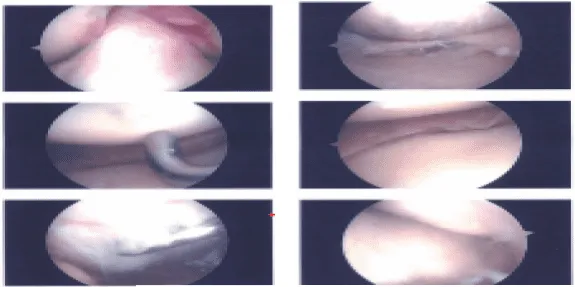

Examination of the medial tibiofemoral compartment showed a complex tear of the posterior horn of the medial meniscus along with grade 2 to grade 3 osteoarthritis of the medial femoral condyle.

Debridement of the meniscus was done with use of shaver and biters. Debridement chondroplasty was also performed with the use of a shaver. Examination of the intercondylar notch showed intact ACL. Examination of the lateral tibiofemoral compartment showed intact meniscus and cartilage.

Examination of the patellofemoral compartment showed grade 3 to grade 4 osteochondral lesion of the lateral facet of patella. Trochlea was intact. Debridement of the patella was done with the use of a shaver.

Arthroscope was inserted through the medial portal and shaver was inserted to the lateral portal and further balancing of the medial meniscus as well as chondroplasty of the patella was performed. Final pictures were taken and saved. Knee was thoroughly irrigated and drained.

Intraoperative images